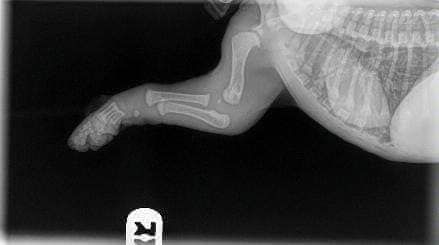

Leurs os ne se touchent même pas encore. Ils marchent si gentiment avec de grosses pattes souples et un mouvement bancal parce que leurs articulations sont entièrement constituées de muscles, de tendons, de ligaments recouverts de peau. Rien ne s'emboîte étroitement ou n'a encore de véritable prise.

Lorsque vous les faites courir de manière excessive ou ne restreignez pas leur exercice pour les empêcher d'en faire trop pendant cette période, vous ne leur donnez pas la chance de grandir correctement. Chaque grand saut ou course de rebond excitée provoque des impacts entre les os. En quantités raisonnables, ce n'est pas problématique et c'est l'usure normale dans laquelle chaque animal s'engage.

Mais lorsque vous laissez le chiot sauter de haut en bas du salon ou du lit, l'emmener pour de longues promenades / randonnées, vous endommagez cette articulation en formation.